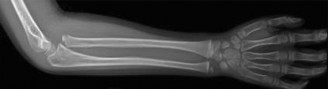

Fractures of the proximal tibial epiphysis demand heightened vigilance due to their intimate anatomical relationship with the popliteal artery.

2. Vascular Proximity: The popliteal artery is firmly tethered posteriorly by the fibrous arch of the soleus muscle. When the proximal tibial shaft is displaced posteriorly in Salter-Harris Type I and II fractures, the artery is stretched over the sharp metaphyseal ridge, leading to intimal tearing, thrombosis, or complete transection.

Fig. 33-173: Salter-Harris type I and II fractures with posterior displacement of the tibial shaft may severely injure the popliteal artery.

Wozasek et al. reported that 13% of patients with proximal tibial physeal injuries exhibited peripheral ischemia. Immediate vascular assessment (Ankle-Brachial Index, Doppler ultrasound, or CT angiography) is mandatory for any displaced proximal tibial fracture.